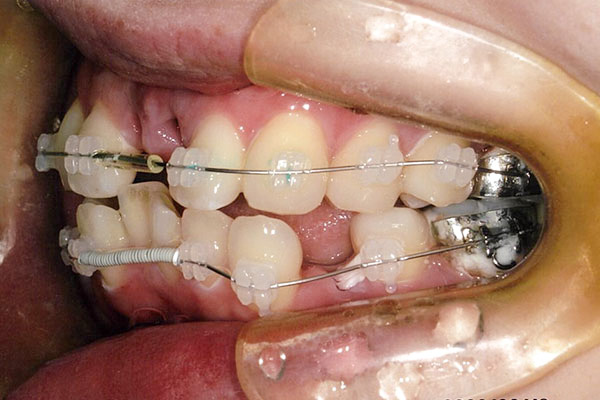

1年3ヶ月後